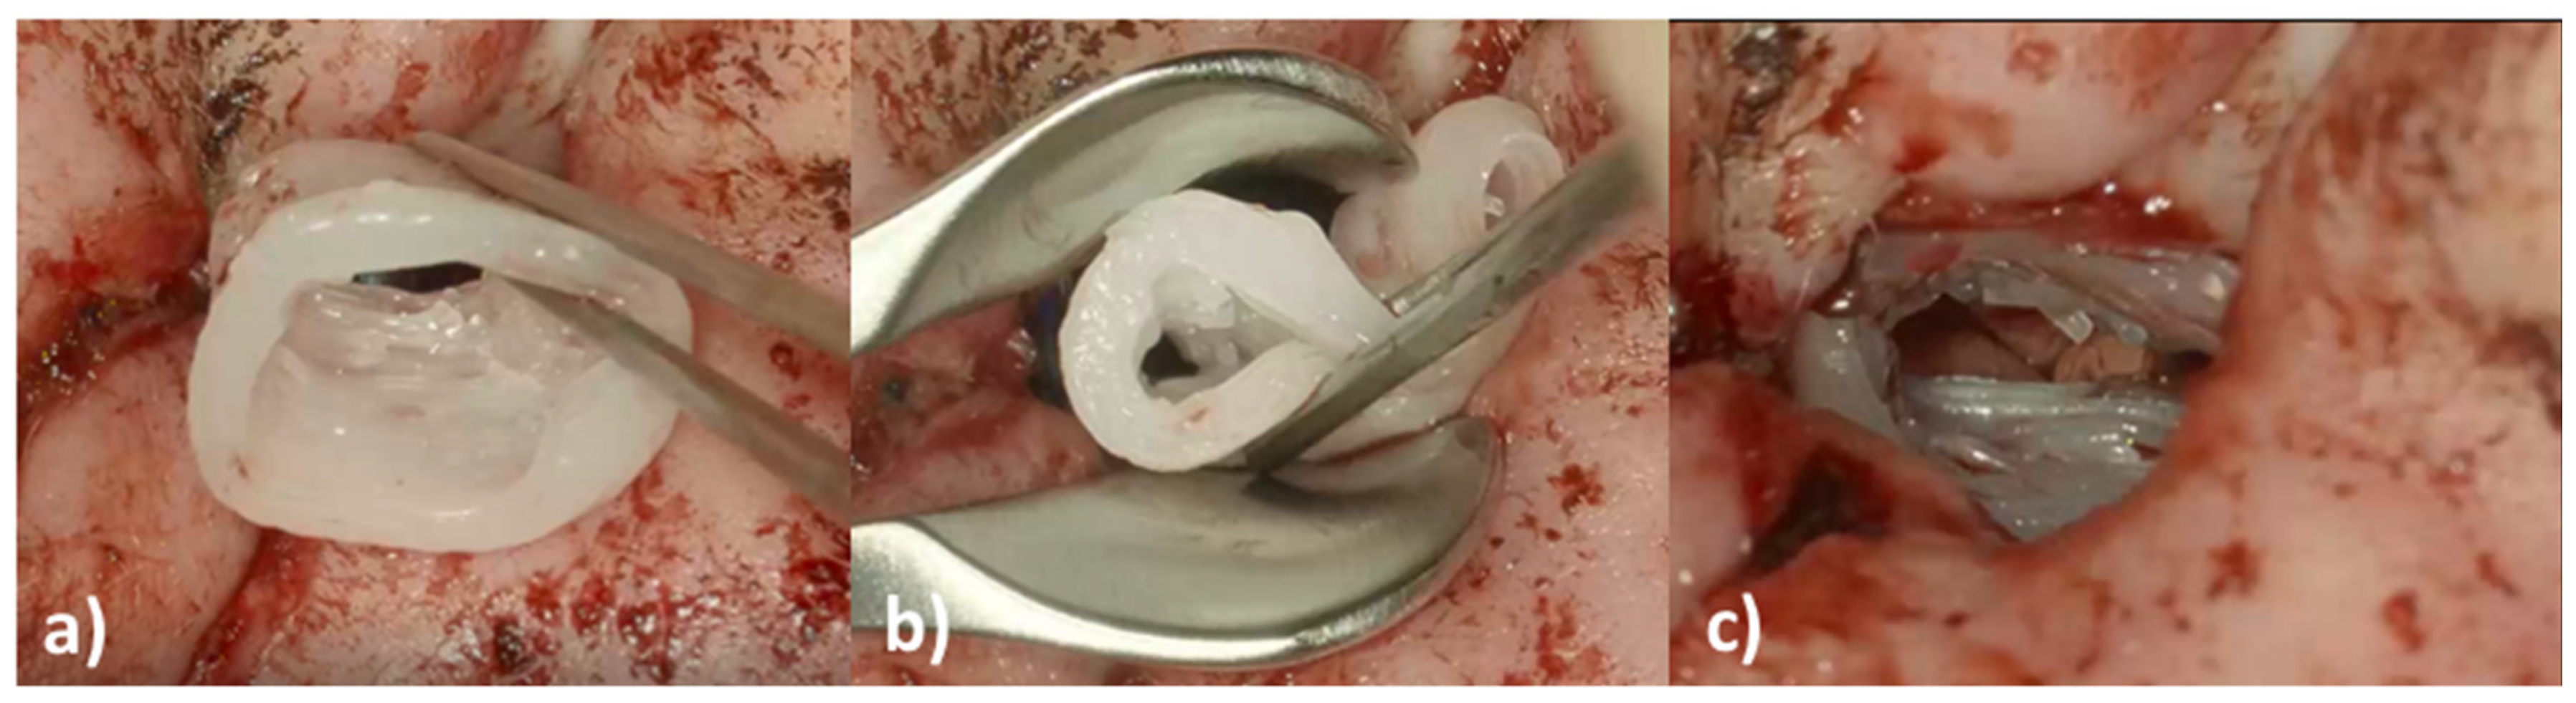

On the day of surgery, the patient underwent canaloplasty with removal of the restenosis on the right EEC under general anesthesia. Due to the patient history of three TM reconstructions a total reconstruction of the TM was performed using Tutoplast® Fascia lata and perichondrium. Then the EECI was inserted using forceps (Figure 8a,b) with ease. The distal end of the implant was placed with some distance to the tympanic ring and the proximal end rested on the opening of the EEC (Figure 8c).

Figure 8. Intraoperative images of the insertion of the 3D-printed, individualized, drug-releasing EECI. (a) After surgically removing the stenosis of the EEC, the EECI was inserted in the right position according to the patient’s anatomy; (b) the texture of the implant was deformable for better handling while insertion with the forceps; (c) perfectly fitted implant in the EEC of the patient.